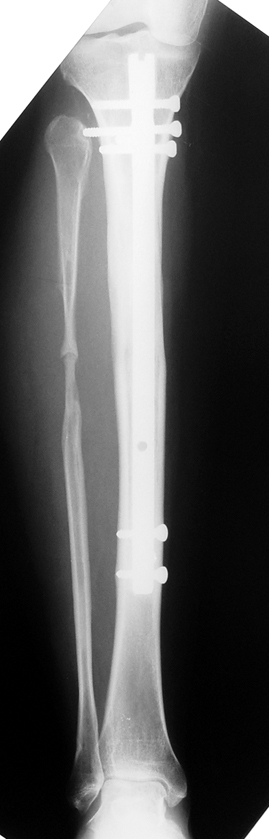

2. Step:

The application of the external fixator: Three Schanz screws are placed distally and three screws are placed proximally. At least 1 mm of distance shall remain between the screws and the nail.

Postoperative care: Distraction is commenced at day 10. 0,25 mm of lengthening is perfomed 4 times daily (every 6 hours). Hip and knee joint motion exercises begin at 1-2. day postoperatively. For many years, the treatment of lower extremity shortness has been very hard for the patient and the surgeon. The techniques developed after the introduction of Ilizarov’s distraction osteogenesis concept have pioneered a new era, and have been considered to be procedures in which previous complications are encountered much less frequently.

In selected cases, we prefer to use a combination of a unilateral dynamic axial fixator and an interlocked intramedullary nail, in order to protect the length and alignment after the completion of the lengthening procedure. As a prerequisite for this technique, the narowest diameter of the medullary cavity shall be wider than 7 mm and the length of the nail segment distal to the osteotomy site shall be at least 8 cm. after the completion of the lengthening procedure.The intramedullary nail neutralizes shear and bending forces on femur during lengthening, shortens external fixation time, and protects newly formed bone against fractures. In our series, subtrochanteric osteotomy was performed in one case. No varus angulation occured despite the intramedullary nail.

The combination of intramedullary anil and dynamic axial external fixator is harder as a technique than Standard Ilizarov applications. However, it is stil appealing due to the following advantages: shortening of the duration of external fixation, protection against refracture, early rehabilitation, gaining maximum range of motion and daily quality of life. These advantages are more important than disadvantages such as increased cost, increased blood loss and potetntial deep infection. All in all, we believe that the technique of femoral lengthening over an intramedullary nail is a safe and reliable method and provides advantages over standard Ilizarov aplications.